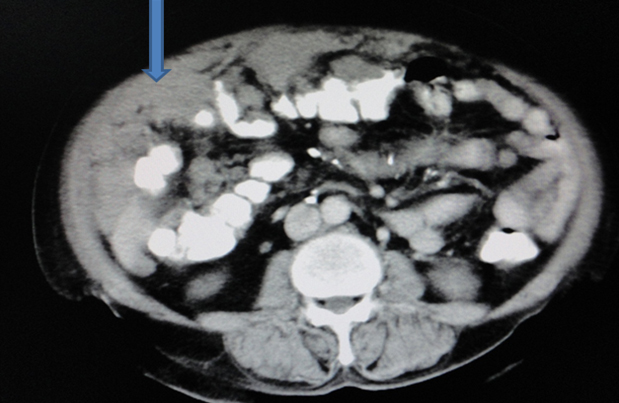

Stage 3: peritoneal implants outside pelvis or inguinal or retroperitoneal lymphadenopathy. Implants can be omentum, liver, parietal peritoneum. Peritoneal dissemination is characterised by peritoneal thickening, nodular lesion, stellate nodules located within mesentery or omentum. Stage 3a, b, c differ in size of lesion- 3a-tumour grossly limited to pelvis and gross ascites; 3b-peritoneal implant 2cms or less; 3c-implant size is more than 2cms . Retroperitoneal and inguinal adenopathy qualifies as stage 3c (Figures 6, 7 & 8).

Figure 8: Two different cases of carcinoma of ovary with omental and peritoneal thickening stage 3.